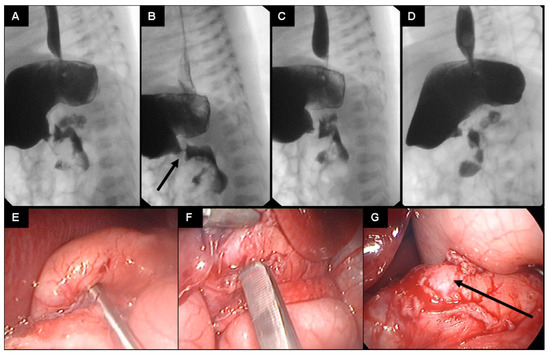

Since the general sonographic criteria for infantile HPS were not met [1] and the child’s clinical condition did not improve, an upper gastrointestinal contrast study was scheduled for the sixth postnatal day. An extremely narrowed and non-peristaltic pylorus with only minimal contrast fluid passing through and with the typical “string sign” of HPS was found (Figure 2A–D). This led to the indication for laparoscopic exploration performed on the seventh day of life.

Figure 2.

(A–G): Sequences of the upper gastrointestinal contrast study (A–D) of the presented preterm infant on day 6 of life (a water-soluble nonionic gastrointestinal radiopaque agent was used). A narrowed pyloric canal presenting as a typical “string sign” is seen (arrow in (B)). Only a minimal passage of the contrast agent is seen during the 20 min duration of the study. Intraoperative pictures showing congenital hypertrophic pyloric stenosis (E) and pyloromyotomy (F,G) (arrow pointing at pyloric mucosa).

Abdominal access is achieved by the open technique through the upper left umbilical quadrant. A 5 mm trocar is inserted and sutured to the fascia. Pneumoperitoneum is set at 5 mmHg. A 5 mm optic is used to inspect the abdominal cavity. Trocarless insertion of the grasper in the right lateral abdomen and trocarless insertion of the knife in the left lateral abdomen. Pyloromyotomy of the thickened pyloric muscle was performed after no other pathologies were found (Figure 2E,F). The procedure is terminated when the mucosa protrudes through the incision (Figure 2G).